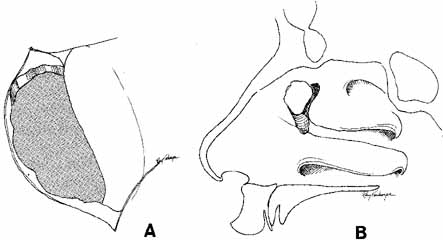

is aided by irrigation with 0.5 mL of an antibiotic steroid solution.  Fig. 19 Probing and irrigation of the nasolacrimal system. Hydraulic pressure is

used in an attempt to force fluid through the obstruction at the valve

of Hasner. If this attempt is unsuccessful, the cannula is slipped

down to the point of obstruction and pushed through gently but firmly. Dye

is injected from the syringe, and the patency of the system is confirmed

by suctioning the dye from the inferior meatus with a soft pediatric-size

plastic suction catheter. Fig. 19 Probing and irrigation of the nasolacrimal system. Hydraulic pressure is

used in an attempt to force fluid through the obstruction at the valve

of Hasner. If this attempt is unsuccessful, the cannula is slipped

down to the point of obstruction and pushed through gently but firmly. Dye

is injected from the syringe, and the patency of the system is confirmed

by suctioning the dye from the inferior meatus with a soft pediatric-size

plastic suction catheter.